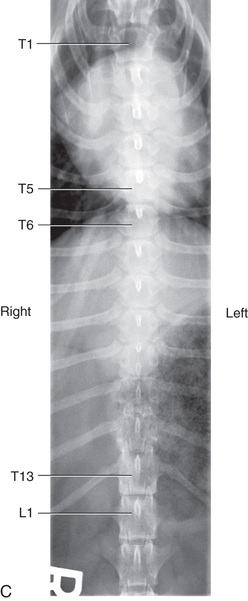

However, in spite of the limitations, proper survey vertebral radiographs are a valuable tool for those patients who have suffered spinal injuries and present with paresis or paralysis, either partial or complete. In addition, survey radiographs can demonstrate many of the signs consistent with intervertebral disk protrusion. Common intervertebral disk protrusion sites are T12 to T13, T13 to L1, C2 to C3, and C3 to C4.1

High-quality images are needed to see subtle changes in bone opacity, shape, and angulation of the vertebrae or vertebral column1,2 (Table 20.1). The common views of this portion of the axial skeleton are the lateral (L) and ventrodorsal (VD) views of the cervical, thoracic, thoracolumbar, lumbar, lumbosacral, sacral, and caudal vertebrae. Depending on the size of the patient, a full survey study is either four or five images of each orthogonal view.